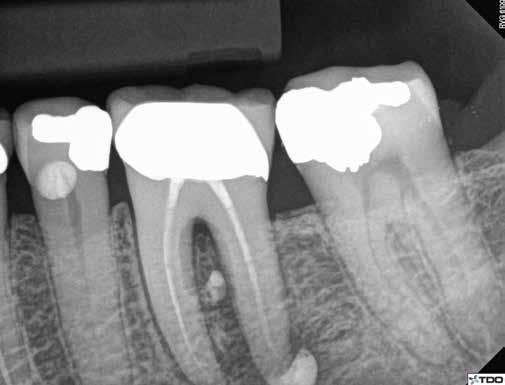

9. a–j. ábrák: A szuvas lézión és a meglévő restaurátumon keresztül történő mezializált és distalizált hozzáférés (a–f). A fogak restaurálása közvetlenül a gyökértömések elkészítése után történt. Az egyéves kontroll során készített röntgenfelvételen a gyógyulás jelei láthatóak, annak ellenére, hogy a gyökércsatornák feltágítása konzervatív módon történt, és a pulpakamra tetejének több mint fele megőrzésre került (g–j). (Dr. Viraj Vora esetei)

ményeképpen számtalan új eszköz vált elérhetővé. A teljesség igénye nélkül ide tartoznak a modern rugalmas, martenzites, hőkezelt, regresszív konicitású NiTi gépi tágítók, amelyek előre meghajlíthatóak (8. ábra), a nagyobb fokú nagyítás és megvilágítás, valamint azok a kisméretű fúrók, amelyek lehetővé teszik a gyökércsatornabemenetek egyenes vonalú hozzáférés nélkül történő feltárását. A rendelkezésre álló kétdimenziós és háromdimenziós (CBCT) röntgenfelvételeket is fel lehet használni a hozzáférési nyílás tervezése és a pulpakamra mélységének megbecslése során. A 7. a–d és 9. a–j ábrák a meglévő restaurátumok és szuvas léziók által meghatározott, mezializált, illetve distalizált hozzáférést illusztrálják. A fogbélhez egy buccálisan vagy linguálisan elhelyezkedő szuvasságon vagy restaurátumon keresztül is hozzáférhetünk (10. a–f és 11. a–f ábrák)